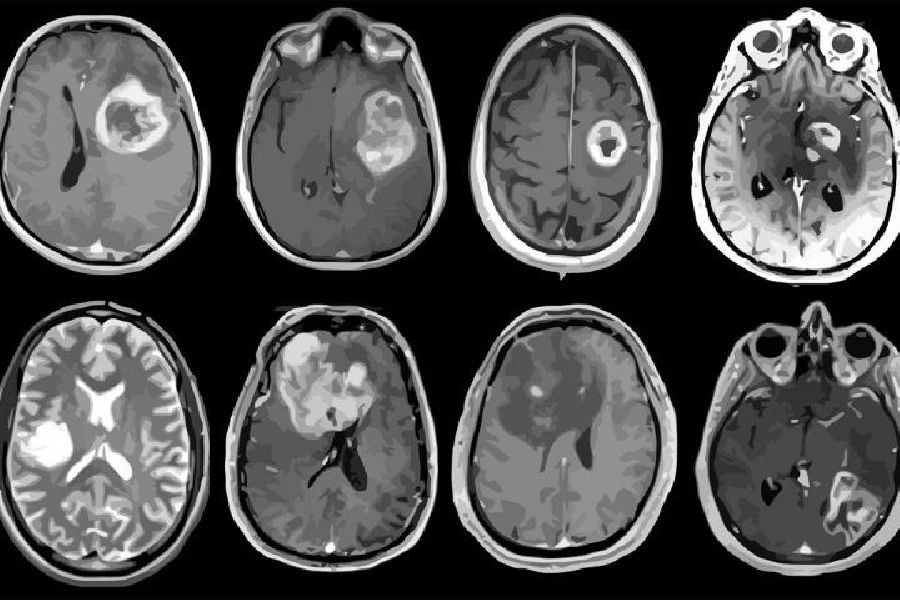

Un modelo de aprendizaje profundo clasifica los tumores cerebrales con una sola resonancia magnética

Un equipo de investigadores de la Escuela de Medicina de la Universidad de Washington, en Estados Unidos, ha desarrollado un modelo de aprendizaje profundo que es capaz de clasificar un tumor cerebral como uno de los seis tipos comunes utilizando una sola resonancia magnética 3D, según un estudio publicado en `Radiology: Artificial Intelligence`.

Los seis tipos de tumores intracraneales más comunes son el glioma de alto grado, el glioma de bajo grado, las metástasis cerebrales, el meningioma, el adenoma hipofisario y el neuroma acústico. Cada uno de ellos se documentó a través de la histopatología, que requiere la extracción quirúrgica de tejido del lugar donde se sospecha que hay un cáncer y su examen al microscopio.

Según Chakrabarty, los enfoques de aprendizaje automático y profundo que utilizan datos de resonancia magnética podrían automatizar potencialmente la detección y clasificación de los tumores cerebrales. "La resonancia magnética no invasiva podría utilizarse como complemento, o en algunos casos, como alternativa al examen histopatológico", explica.